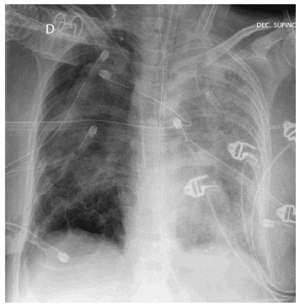

Se trata de una mujer de 36 años con antecedentes de hemosiderosis pulmonar idiopática que ingresa en la Unidad de Cuidados Intensivos (UCI) por insuficiencia respiratoria aguda secundaria a hemorragia alveolar. Es intubada y conectada a ventilación mecánica. A la semana de su ingreso se mantiene un deterioro grave del intercambio gaseoso (PaO2/FiO2 < 100), con infiltrado alveolar bilateral y sin evidencia de nuevo sangrado alveolar. Es diagnosticada de síndrome de distrés respiratorio del adulto secundario a hemorragia alveolar. A los 10 días la paciente sufre neumotórax bilateral y recidivante durante 21 días, a pesar de la colocación de 5 tubos de drenaje torácicos (fig. 1). Se realiza una tomografía computarizada (TC) de tórax en la que se evidencia neumotórax anterior derecho, con desplazamiento de mediastino, con neumatoceles diseminados y lesión difusa alveolointersticial bilateral (fig. 2). La paciente falleció en situación de hipoxemia refractaria tras 45 días de ingreso en UCI.

Fig. 1